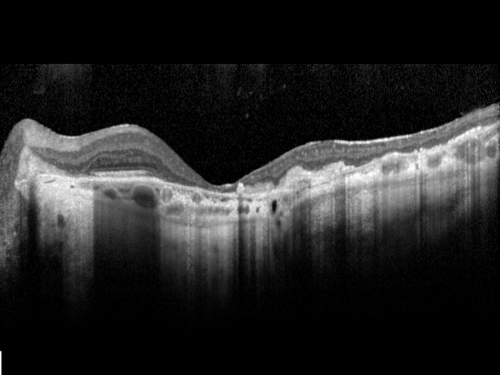

Ocular Histoplasmosis both Eyes - Laser Right Eye Only SD-OCT

58-year-old woman who lost vision as a child in the left eye from ocular histoplasmosis.  She used to play in her attic and she was told by her pulmonary doctor that is probably where she picked it up.  She had laser in the right eye for a leaky lesion back in 1990.  OD 20/25,  OS 20/200.